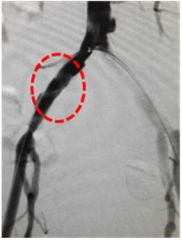

介入治疗后,血流顺利通过原闭塞段,左侧上肢血压恢复正常,头晕症状消失。

治疗后